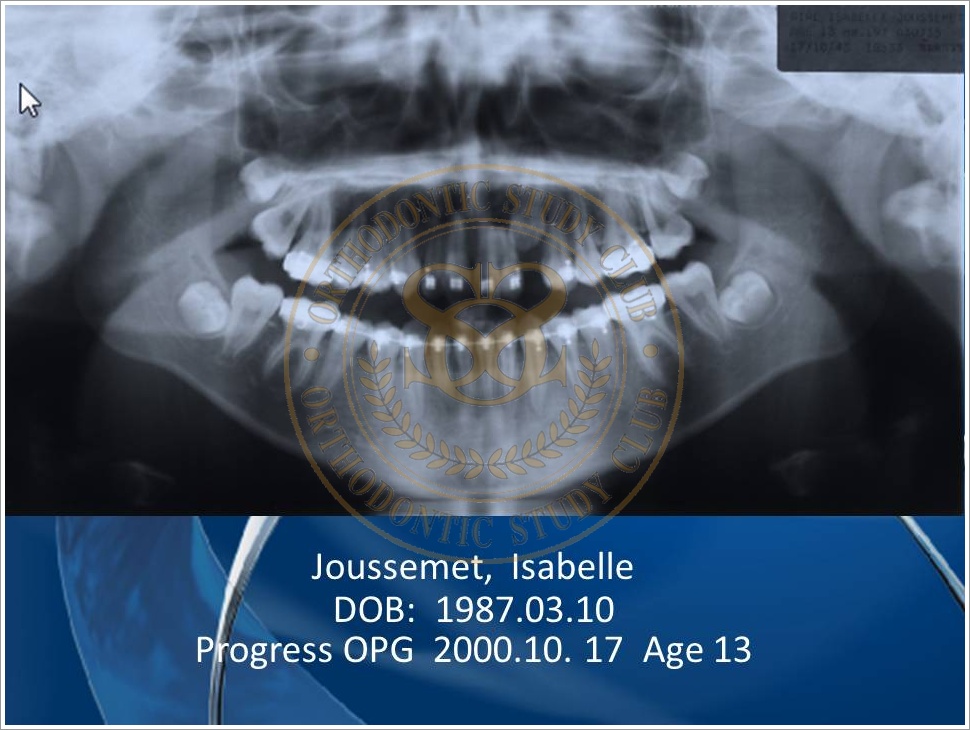

Treatment of Pseudo Class III (Class I Molar Relationship) and management of the embedded maxillary canine (Pt. Miss J.I.)